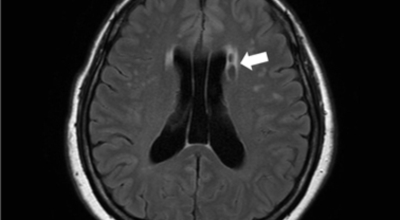

뇌경색의 경색이란 허혈성 괴사를 말해요. 여기서 허혈이란 혈관이 막히는 것을 말하고 괴사는 말 그대로 일부가 죽는 것을 말하는데 뇌경색의 경우 뇌의 혈관이 막혀 뇌세포 일부가 죽는 걸 의미해요. 뇌혈관이 막혔다 해서 혈액 공급이 안되는것은 또 아니에요.

막힌 혈관으로도 혈액이 공급되긴 하나 혈관이 막혀있어 혈액을 보내긴 하나 제대로 흐르지 못하고 혈액이 쌓이고 축적되어 물풍선에 물이 꽉 차서 터지듯 뇌혈관이 터지는 경우가 일어날 수 있는데 이를 뇌출혈 이라고 해요. 물론 외상으로 인한 뇌출혈도 있지만 이처럼 뇌경색으로 인해 혈관이 막혀 터지는 경우도 있어요.